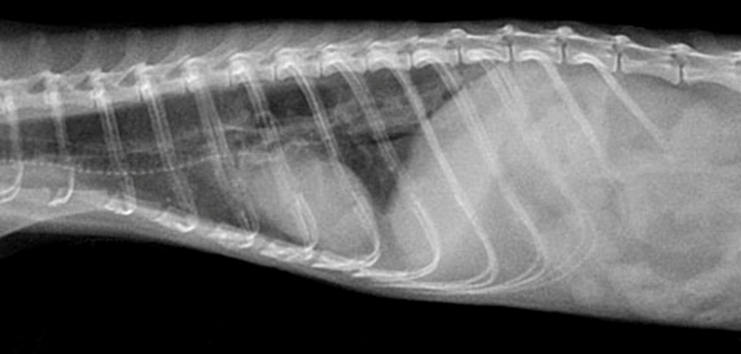

X線検査で食道が拡大(拡張)し、正常な運動性が欠如している状態を指しますが。

鑑別診断には食道または胃腸の異物、胃炎、および呼吸器疾患が含まれます。X線検査では食道が拡張あるいはガスが貯留しており、確定診断のために硫酸バリウムまたはイオヘキソール(経口投与 [PO] で 8~10 mL/kg)を投与します。フェレットは注射器で強制的にバリウムを摂取しますが、食道破裂の可能性がある場合には、バリウムの代わりにイオヘキソールを使用します。造影剤が食道の輪郭を描出し、巨大化していることで診断されます。